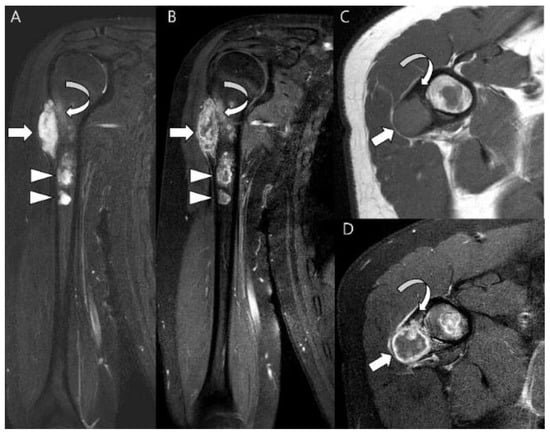

3.3. Distinction between ACT/CS1 and High-Grade Chondrosarcoma

- Jain, V.; Oliveira, I.; Chavda, A.; Khoo, M.; Saifuddin, A. MRI differentiation of low-grade and high-grade chondrosarcoma of the shoulder girdle, chest wall and pelvis: A pictorial review based on 111 consecutive cases. Br. J. Radiol. 2021, 94, 20201404. [Google Scholar] [CrossRef] [PubMed]

- Douis, H.; Singh, L.; Saifuddin, A. MRI differentiation of low-grade from high-grade appendicular chondrosarcoma. Eur. Radiol. 2013, 24, 232–240. [Google Scholar] [CrossRef] [PubMed]